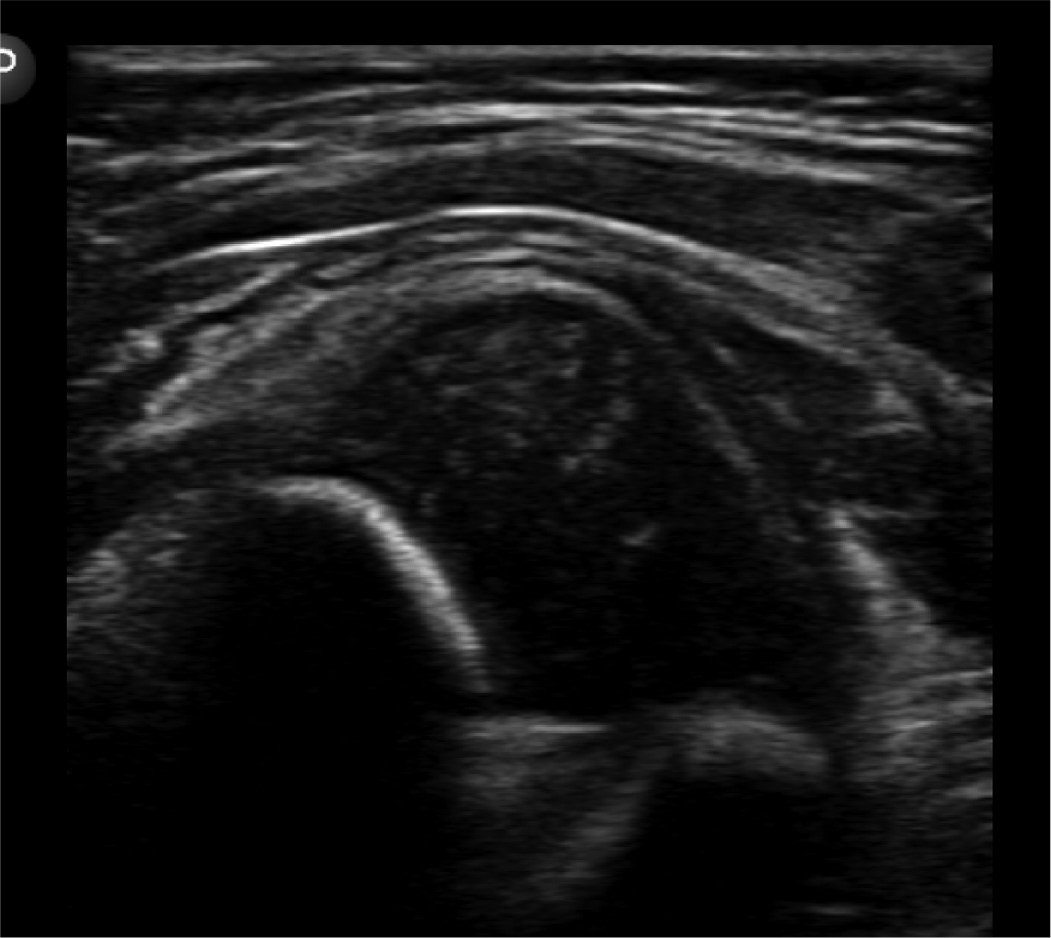

Step 3. Determine Whether the Socket is Deep or Shallow10

A coronal view is obtained by rotating the transducer 90 degrees, producing an image analogous to an AP of the pelvis (although it is rotated 90 degrees on its side). To accurately assess acetabular development, these coronal images should be captured with a perfectly flat ilium, from which measurements can be constructed. A line is drawn along the lateral border of the ilium, akin to the straight iliac line, which should intersect the femoral head with at least 50% of the head below the line, with smaller values suggesting a shallow socket. This line provides an objective measure of the coverage. A second line can be drawn along the bony acetabular roof to the edge of the acetabulum. The angle between the baseline and this line is the acetabular roof angle. This angle should always be greater than 60 degrees and should increase progressively with age.

Using a Graf table (Figure 7) with a phantom baby (Figure 8), one can replicate all exam steps. By following all the steps listed above, on the simulation baby in the lateral decubitus position (Figure 9), one can acquire the skills to understand ultrasound evaluation of morphology. Limitations of using the phantom baby is that it does not allow for a dynamic exam and, although it allows understanding of normal anatomy, the phantom does not although the trainee to identify and measure pathologic findings (Figure 10). Once the trainee is comfortable and demonstrates proficiency with the phantom baby in the Graf table, we recommend practicing the exam with the phantom outside the positioner (Figure 9).

Figure 10. Phantom baby hip on left, real baby hip on right.